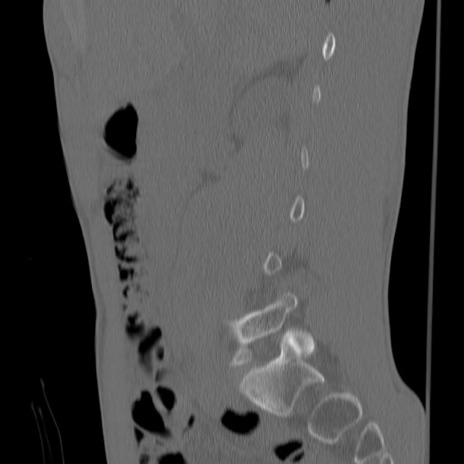

症例3 腰椎CT(矢状断像)

【症例】30歳代男性

【主訴】腰痛

【現病歴】本日旅行先で観光中に、友人と衝突し転倒し受傷。

【身体所見】麻痺なし、右下腿内側前面外側、左下腿内側に知覚鈍麻・しびれ

異常所見と診断は?

腰椎CT